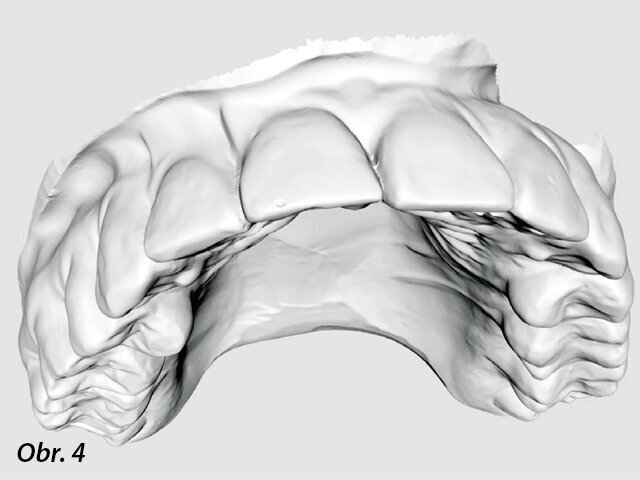

Byly zhotoveny silikonové otisky a vytvořen sádrový zubní model, který byl naskenován (iTero, Align Technology) (obr. 4). CBCT zobrazení i skeny modelů byly vyrovnány a zpracovány pomocí coDiagnostiX. Virtuální kopie vrtáčku s průměrem 1,2 mm a délkou 17 mm (Meisinger) byla vložena do skenů v pozici, která umožnila přístup do identifikovaného systému kořenových kanálků v apikální třetině zubu (obr. 5). Pozice vrtáčku byla zkontrolována ve 3D. Dále byla 3D šablona exportována jako STL soubor a odeslána do 3D tiskárny (Form 2, Formlabs) (obr. 6–9).